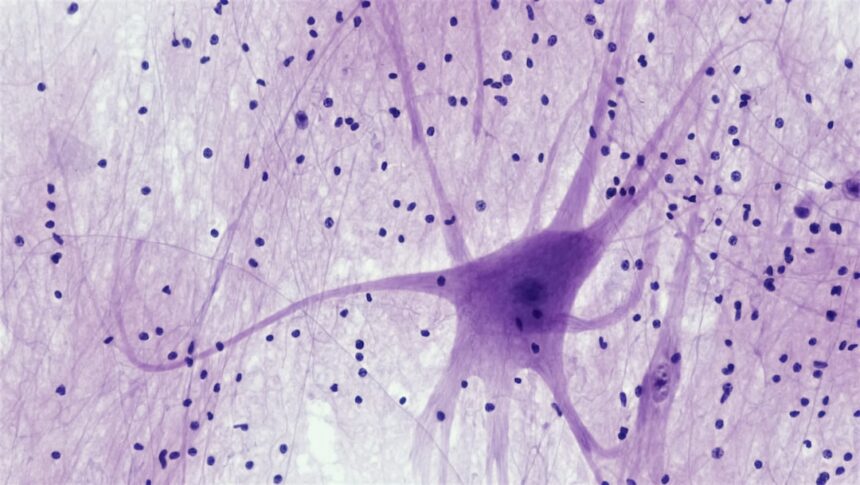

Your brain is an intricate organ that constantly processes information, allowing you to navigate through life. When it comes to perceiving absence, your brain employs a variety of mechanisms to interpret what is not present. This process is not simply about recognizing what is missing; it involves complex cognitive functions that help you make sense of your environment.

Neurological Mechanisms of Non-Existence

The neurological mechanisms that underpin your perception of non-existence are both fascinating and intricate.

For example, the prefrontal cortex plays a significant role in higher-order thinking and decision-making, allowing you to evaluate situations where something is missing.

Meanwhile, the parietal lobe helps integrate sensory information, contributing to your understanding of spatial relationships and the absence of objects within that space. Neuroimaging studies have revealed that specific neural pathways are activated when you encounter situations involving non-existence. These pathways facilitate communication between different brain regions, enabling you to form a coherent understanding of what is absent.

Neural Pathways Involved in Processing Absence

The neural pathways involved in processing absence are complex and interconnected, reflecting the multifaceted nature of human cognition. When you encounter a situation where something is missing, various brain regions collaborate to create a comprehensive understanding of that absence. The anterior cingulate cortex, for example, plays a role in error detection and conflict monitoring, helping you recognize discrepancies between what you expect to find and what is actually present.

Additionally, the hippocampus is crucial for memory formation and retrieval, allowing you to draw on past experiences when assessing absence. This interplay between different brain regions highlights the dynamic nature of cognitive processing related to non-existence. As you navigate through life, these neural pathways continuously adapt and evolve based on your experiences, shaping how you perceive and respond to absence in both familiar and novel situations.